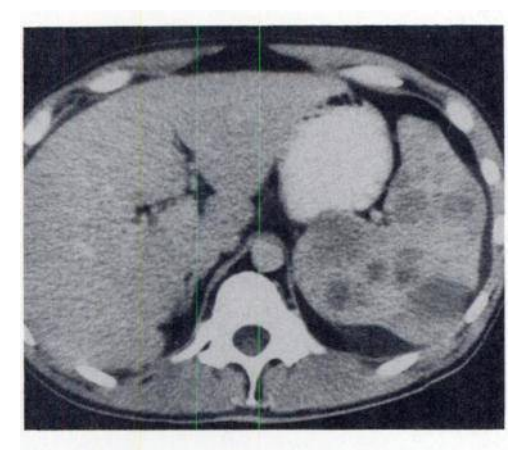

The liver is at the upper limit of normal in size and her main portal vein is enlarged measuring 17 mm in diameter. The splenic vein is also enlarged. Focal fatty change is again demonstrated. No focal lesions. The remainder of the upper abdominal solid viscera are unremarkable, with no other infarcts identified. No lymph node enlargement and no focal osseous lesion.

Conclusion

Splenic infarcts is confirmed and presumably accounts of the patient’s presentation. The cause of the patient’s splenomegaly is uncertain, although the main portal vein and splenic vein do appear enlarged as does the liver raising the possibility of portal hypertension. Incidental adrenal adenoma.

Case Discussion

This case highlights the need to remember the differential of regional pain when assessing CT KUB for nephrolithiasis.